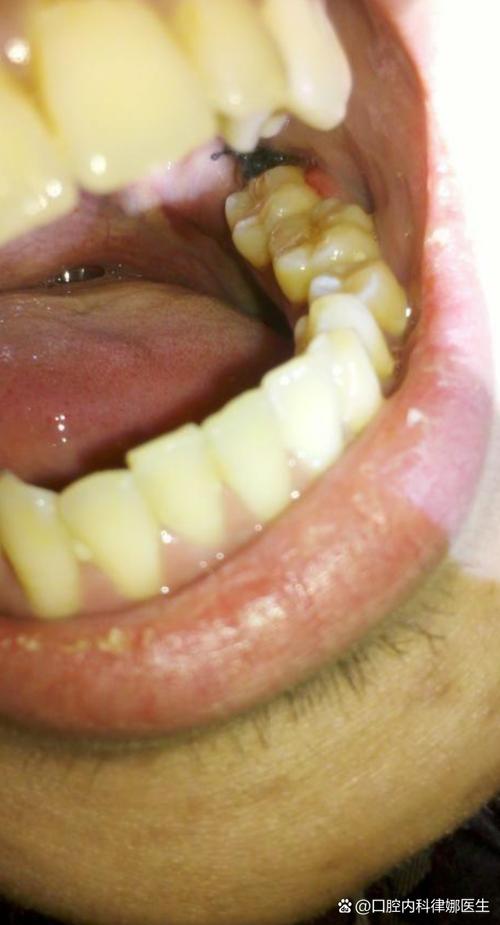

(图片来源网络,侵删)

(图片来源网络,侵删)- 不要用手指、牙签、镊子等尖锐物去掏,这些工具会带入细菌,并极易破坏脆弱的血凝块。